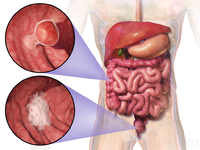

سرطان القولون والمستقيم

مقالة مفصلة: سرطان القولون والمستقيم

| سرطان القولون والمستقيم | ||

| معدل الانتشار | 9.4 مليون (2015)[7] | |

| معدل البقاء 5 سنوات | 65% (الولايات المتحدة)[4] | |

| حالات الوفاة | 832.000 (2015)[6] | |

| عوامل الخطورة | التاريخ العائلي لحدوث سرطان القولون والمستقيم في الأسرة؛ سلائل (پوليپات) polyps أو أمراض الأمعاء الالتهابية. تم ربط وجود طفرات جينية نوعية بداء السليلات الغدومي العائلي familial adenomatous polyposis (الذي يمكنه أن يتحول إلى سرطان القولون) وبسرطان القولون والمستقيم الوراثي غير السليلي. ويزداد خطر الإصابة أيضا عند الذين يعيشون في المدن أو المناطق الصناعية. وتتضمن بقية عوامل الخطورة نقص النشاط البدني والتعرض لمواد كيميائية معينة وتناول الأغذية الغنية بالدهون أو قليلة الألياف. | |

| العلامات المنذرة | وجود دم في البراز؛ أيُّ تغيرٍ في عادات التغوط؛ انزعاج معدي عام، فقدان وزن ليس له ما يبرره. | |

| الكشف والتشخيص | يجب إجراء فحص المستقيم بالإصبع وتحرّي الدم في البراز سنويا لكل شخص يفوق الأربعين عاما؛ تنظير السيني sigmoidoscopy كل 3 ـ 5 سنوات بعد سن الخمسين. وإذا اشتُبِه بوجود أي اضطرابات، يمكن إجراء تنظير القولون واستخدام رحضة (حقنة) الباريوم barium enema (للتمكن من رؤية الأمعاء عند التصوير بالأشعة السينية). ويكون الإنذار prognosis سيئا إذا كانت الأمعاء مسدودة أو مثقوبة أو كانت مستويات مواد واسمة marker substances معينة (مثل المستضد الجنيني السرطاني carcinoembryonic antigen والمستضد الكربوهيدراتي 9-19) في مصل الدم مرتفعة قبل العلاج.

| العلاج | الجراحة لإزالة الورم، وأحيانا يضاف إليها المعالجة الشعاعية أو الكيميائية أو كلتيهما. وقد يتحتم في بعض الحالات فَغْر القولون colostomy (عمل فتحة تصريف فيه). وإذا انتشر المرض إلى العقد اللمفاوية، تصبح المعالجة الكيميائية بالفلوروراسيل fluorouracil مفيدة. وبالنسبة لسرطان المستقيم المتقدم والمتوسط الشدة تستخدم المعالجة الكيميائية المترافقة مع المعالجة الشعاعية، ولعل إزالة النقائل من الكبد جراحيا تطيل بُقيا بعض المرضى.